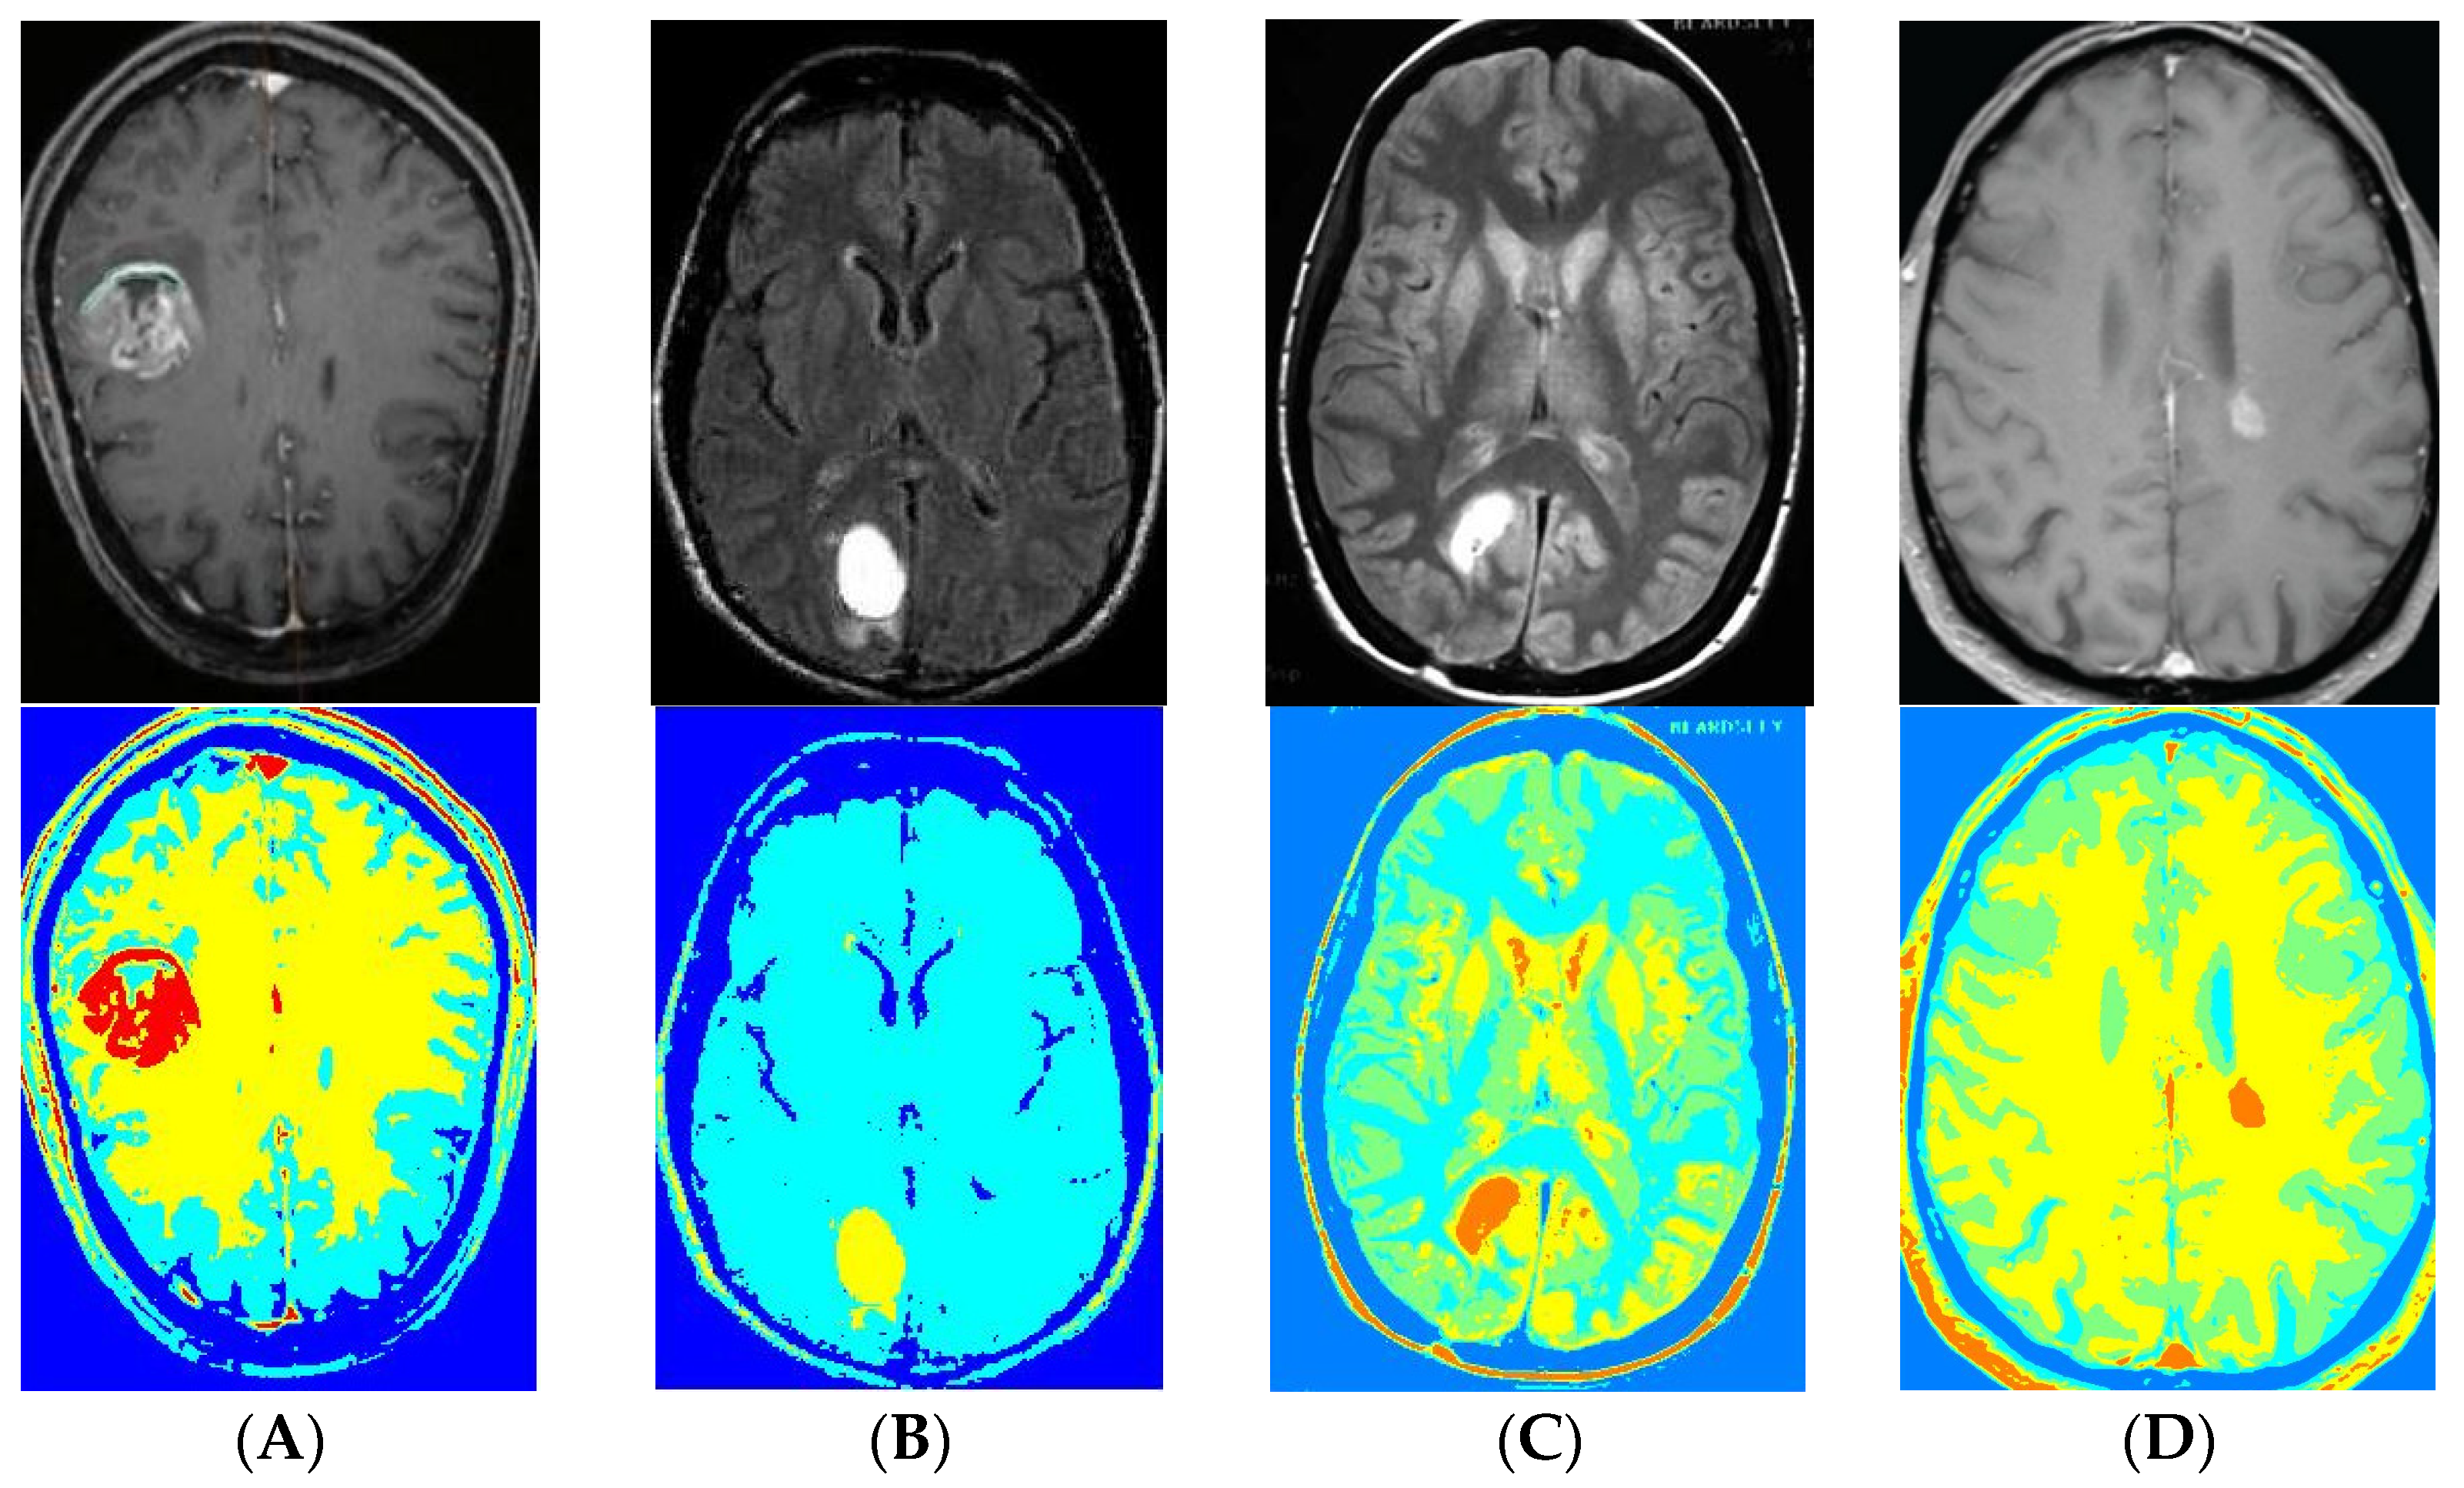

3. Results